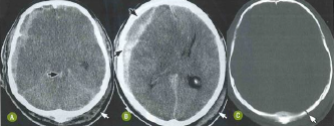

Paciente de 26 anos foi vítima de acidente automobilístico com traumatismo cranioencefálico. Nas imagens tomográficas a seguir, pode-se observar